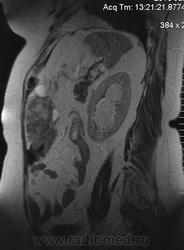

очень характерная картина для метастаза рака яичника, к сожалению.

Не могу достоверно определить локализацию метастаза брюшной полости, вероятно в лимф. узел с инвазией оободочной кишки. Рецидив С-r левого яичника думаю, что с инфильтацией левой стенки прямой кишки и культи влагалища, вторичная лимфаденопатия л/у малого таза. каликопиелоуретероэктазия (инвазия нижних отделов левого мочеточника?) Холедох широковат, но желтухи по внешнему виду нет.

Прорастание левого мочеточника рецидивной опухолью есть 100%, метастаз в большой сальник характерен для рака яичников, как и сигнальные характеристики его. Культя в данном случае шейки матки.